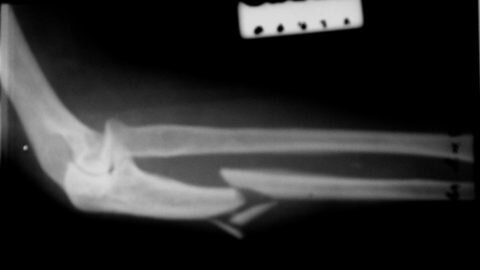

Анатомическое строение Для начала следует подробнее ознакомиться с анатомическим строением этой области. Рука человека в зоне предплечья разделяется на 2 основные части: локтевая и лучевая кость. Перелом левого предплечья код МКБ может сопровождаться повреждением одной или сразу обеих из них. Также отдельно выделяют тело, верхнюю и нижнюю часть обеих костей. На локтевой присутствуют венечный и локтевой отростки, на лучевой – шиповидный. В нижней части формируется лучезапястный сустав, а проксимальной – локтевой...